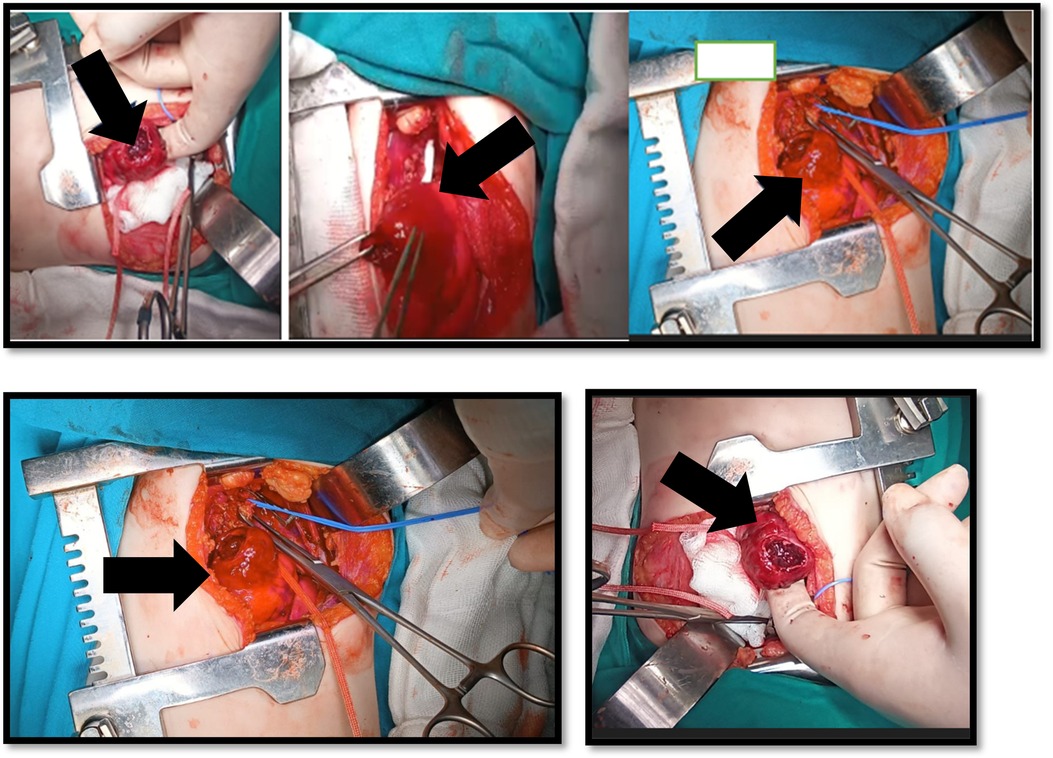

Invasive aspergillosis (IA) is a severe opportunistic infection in immunocompromised children, particularly those receiving chemotherapy for hematologic malignancies. We report a 2-year-old girl with acute lymphoblastic leukemia (ALL) who developed massive hemoptysis during consolidation chemotherapy. Thoracic computed tomography revealed a saccular pseudoaneurysm of the proximal left subclavian artery. Surgical resection and autologous vein graft replacement were performed, and Aspergillus flavus DNA was detected by Aspergillus-specific polymerase chain reaction (PCR) from the resected tissue. The patient received dual antifungal therapy with liposomal amphotericin B and voriconazole, followed by long-term voriconazole prophylaxis, and made a full recovery. This case highlights the importance of considering angioinvasive aspergillosis in immunocompromised children presenting with hemoptysis and lung lesions, and the value of early multidisciplinary management to prevent fatal vascular complications.